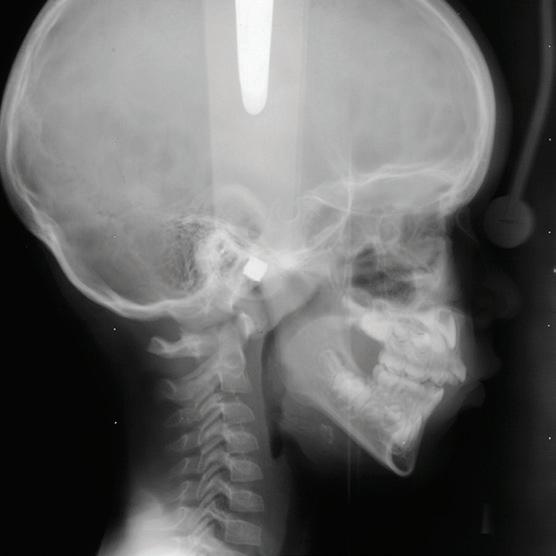

ABOUT THE COLLECTION

With support from the American Association of Orthodontists Foundation (AAOF), nine of the eleven known collections of longitudinal craniofacial growth records in the United States and Canada have joined together to create this web site and its underlying numerical database. Our purpose is to make representative materials from the participating collections available for viewing and further investigation by clinicians, craniofacial investigators, students of human growth, and interested members of the public.

These collections represent the work of hundreds of investigators. They have been gathered, cataloged, and studied over a period

Now, by merging data from the collections, we hope to make possible further collaborative studies that will enrich and refine our knowledge of craniofacial growth in untreated children and adolescents.

CRANIOFACIAL GROWTH LEGACY COLLECTION PROJECT

Presently available on the site are more than 13,000 digital images including 8,700 lateral cephalograms and over 3,000 frontal (PA) cephalograms generated at different ages from 704 cases, gathered from 9 different collections. Summary statistics on case distribution by sex/ gender, age and Angle Class may be found by clicking on “ Statistics” in the About menu.

This entire site is a continually developing resource for orthodontic teaching and research. Its primary role is to serve as a repository for longitudinal records of all types with sufficient numerical documentation to facilitate useful search and querying.